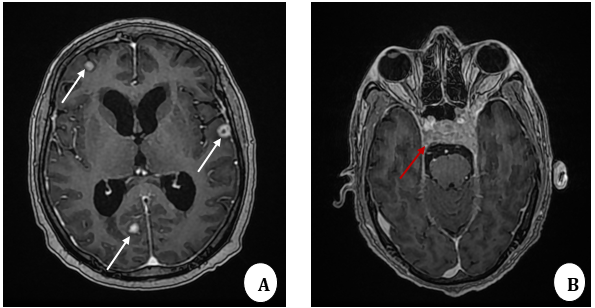

FIGURE 3: MRI brain T1W contrast-enhanced axial images:

A: Enhancing supratentorial soft tissue lesions (white arrows) – Brain metastatic

B: Bony metastatic lesion involving the clivus infi ltrating the left cavernous sinus (red arrow)

MRI brain was conducted due to neurological symptoms. Contrastenhanced MRI brain showed supratentorial brain parenchymal metastatic lesions (Figure 3A) and metastatic involvement of clivus extending into the left cavernous sinus (Figure 3B). Given the extensive systemic spread, surgical resection was not feasible. The patient was managed with systemic chemotherapy and palliative radiotherapy. The patient started systemic multiagent chemotherapy with the standard VAC/IE regimen, consisting of alternating cycles of Vincristine, Adriamycin, and Cyclophosphamide (VAC) with Ifosfamide and Etoposide (IE). Chemotherapy was delivered in an interval-compressed schedule every 2–3 weeks, as recommended in current Ewing sarcoma protocols (NCCN, COG, Euro-Ewing). In addition, palliative radiotherapy for osseous and brain lesions was initiated. Unfortunately, our patient could not bear chemotherapy and disease burden due to extensive disease and succumbed to her disease.